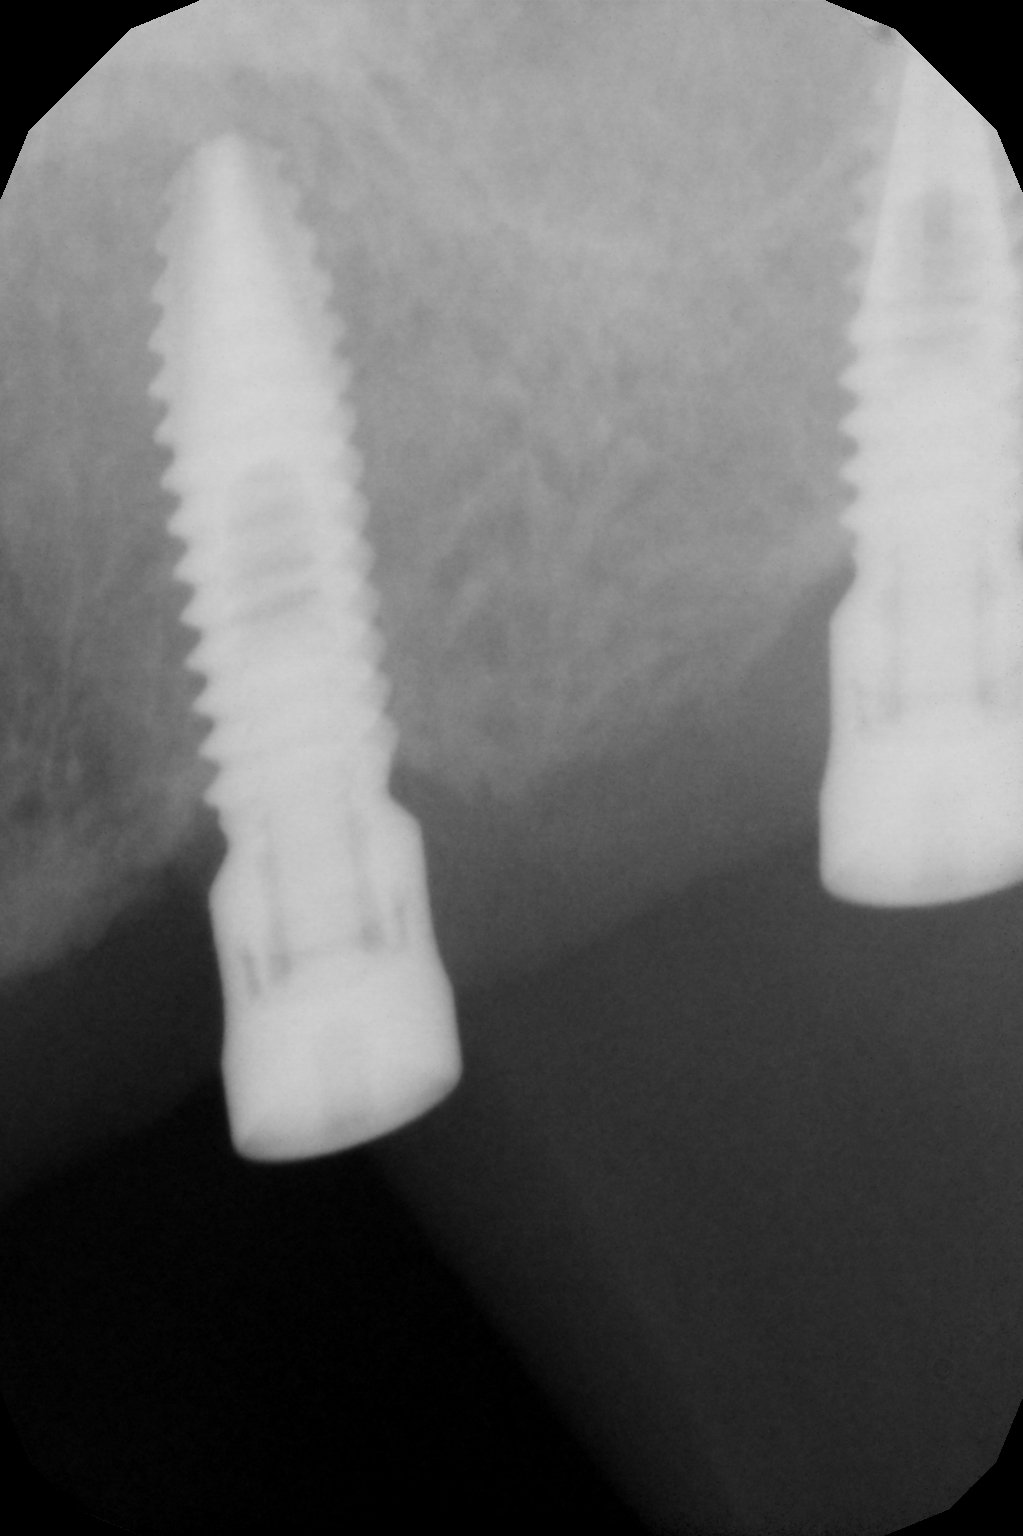

ACUDE PACIENTE DE IDENTAL CON IMPLANTES COLOCADOS EN AGOSTO DE 2017 SIN CARGAR. LA PACIENTE VIENE PARA COLOCAR CORONAS, NO PUEDE ACCEDER A SU HISTORIAL CLINICO. CONEXION HEXAGONAL. PROBAMOS ADITAMENTOS [...]